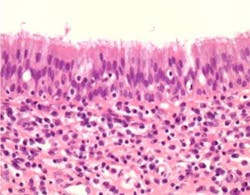

The pathology report identified the specimen as a 1.1 x 0.8 x 0.5 cm inflammatory cyst of the maxilla (figure 12). The patient now exhibits 10 mm of attached gingiva on the facial of tooth No. 3. The recession defect has been completely eliminated by a combination of the SECT graft and the full-coverage restoration (figure 13). The periapical radiograph shows no residual periapical pathology. After one year, the patient continues to be asymptomatic and is functioning well with the tooth.